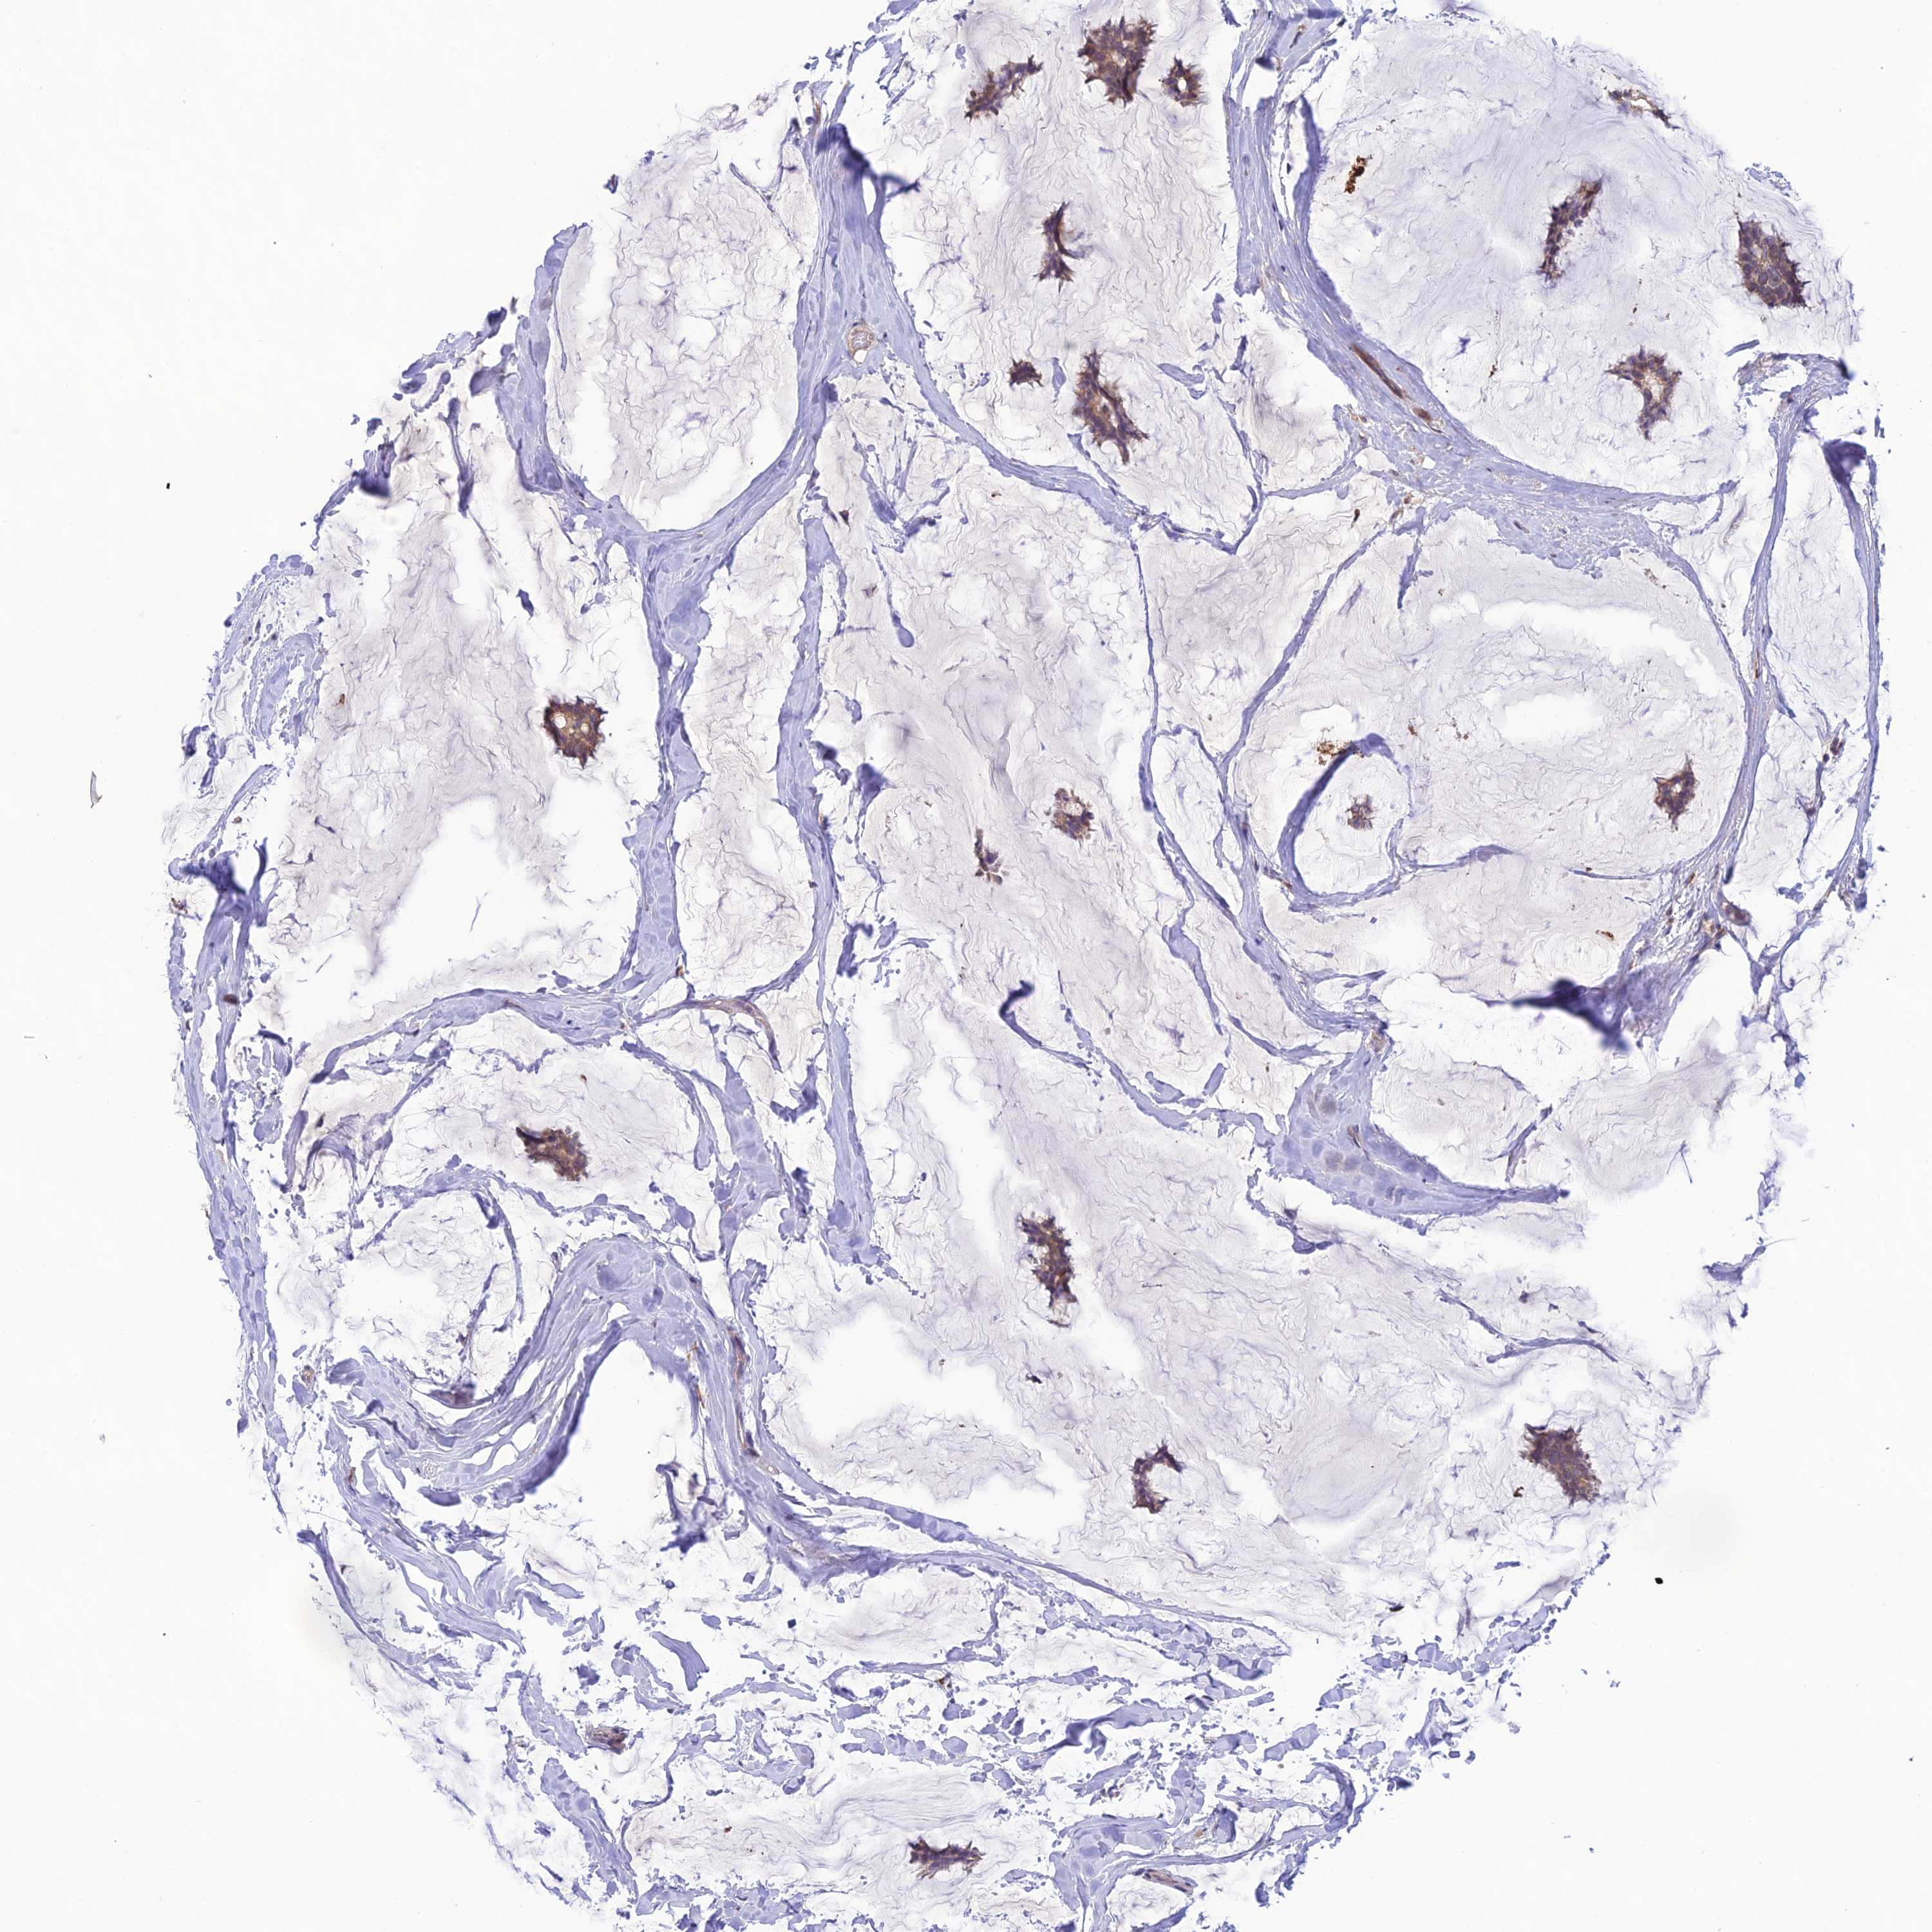

Breast cancer

Human cancer